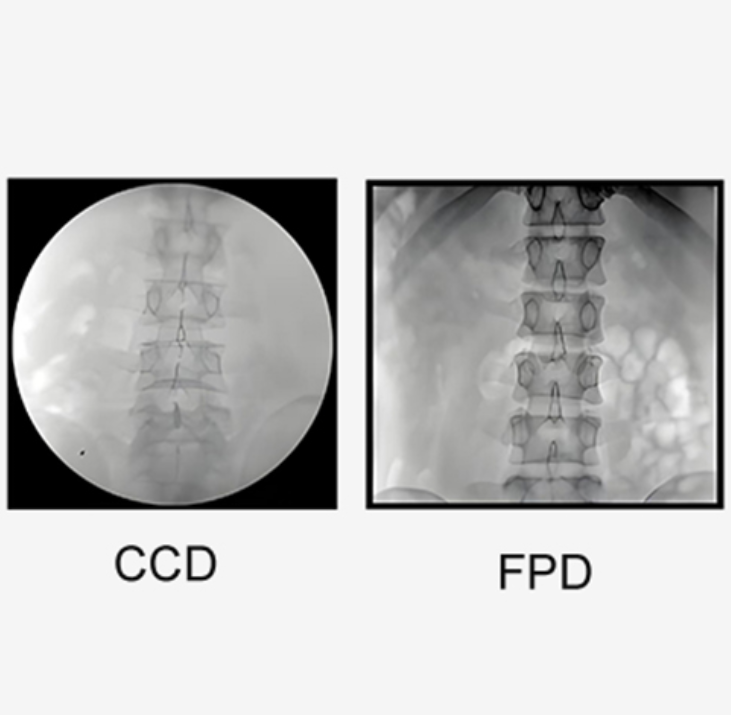

L'FPD sostituisce il CCD, immagini più chiare.